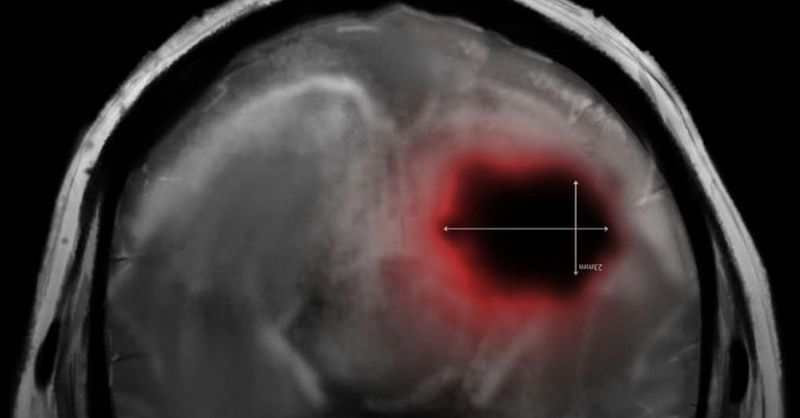

This superfood can prevent brain clots and protect your mental health

Blood clots in the brain can lead to strokes and other serious health problems. But nature gives us a powerful helper: garlic. This small but mighty food has...